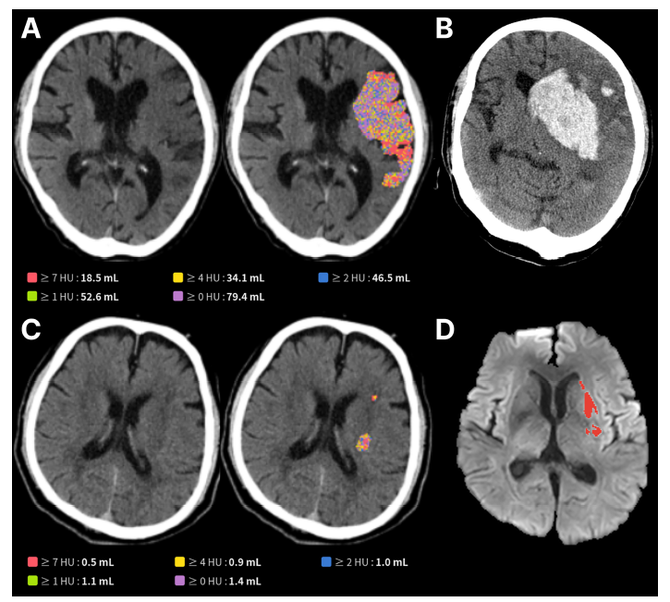

제이엘케이의 AI 모델은 이러한 문제를 해결하기 위해 개발됐다. 다수의 뇌경색 환자 NCCT와 확산강조영상(DWI) 데이터를 학습한 딥러닝 기술을 기반으로, 육안 식별이 어려운 미세한 뇌 손상 영역을 자동 검출하고 그 부피를 정량적으로 분석할 수 있다.

이번 연구는 국내 6개 대형 뇌졸중 센터의 데이터를 기반으로, 총 603명의 혈관 내 재개통술 환자를 대상으로 임상적 유효성을 검증했다.

그 결과, AI가 NCCT 영상에서 분석한 뇌 손상 부피가 클수록 3개월 후 환자의 기능 회복 가능성은 현저히 낮았으며(50mL 초과 시 17.3% vs. 54.2%), 뇌출혈 전환과 같은 심각한 합병증 발생률은 더 높게 나타났다(66.0% vs. 46.3%).

이는 응급실에서 촬영한 기본 CT만으로도 환자의 장기적인 예후를 예측할 수 있음을 보여주는 중요한 과학적 근거다.